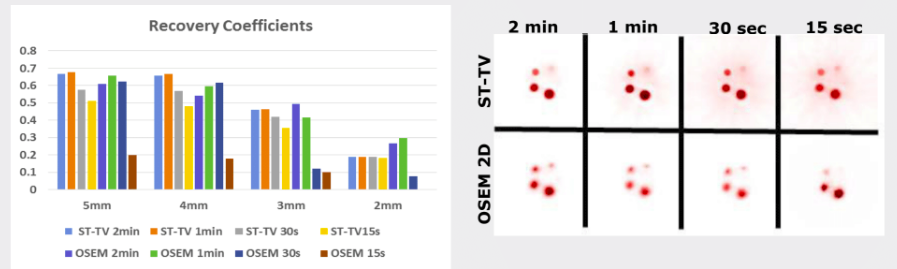

In this work, we propose a novel 4D reconstruction method for PET which is based on spatiotemporal total variation (ST-TV). The ST-TV method takes advantage of image redundancies in 4D and was efficiently implemented using the split Bregman formulation, which has been shown to be optimal for decreasing noise while maintaining image quality. To evaluate the proposed approach we simulated data for a dynamic numerical phantom with different number of counts to mimic high and low Signal-to-Noise Ratio (SNR) scenarios.

| ABSTRACT | Dynamic PET images suffer from low signaltonoise ratio (SNR), especially for fast contrast uptake measurements due to the small number of counts available in those time frames. In this work, we propose a 4D reconstruction method based on spatiotemporal total variation (STTV) which takes advantage of image redundancies in 4D. The 4D STTV method was efficiently implemented using the Split Bregman formulation, which has been shown to be optimal for decreasing noise while maintaining image quality. To evaluate the proposed approach we acquired listmode data from a NEMA image quality phantom in a preclinical PET/CT scanner. |